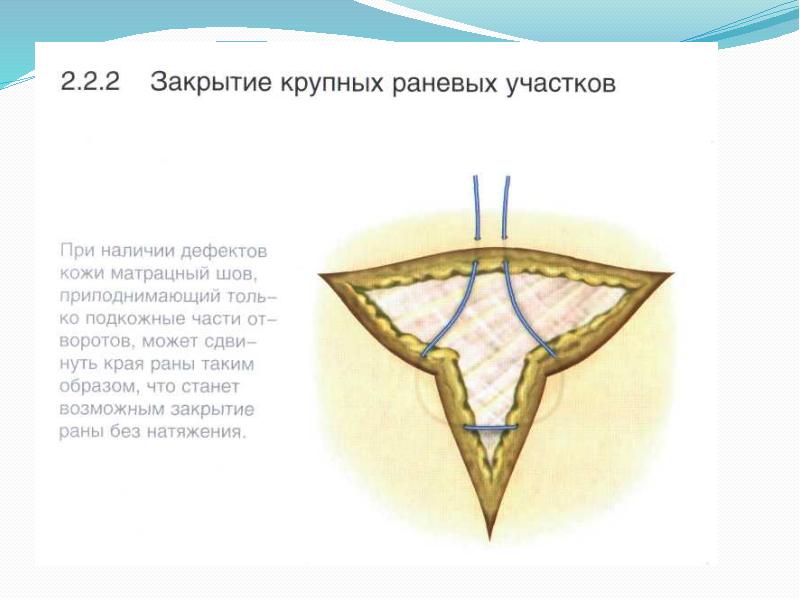

- 46. Зашивание асимметричных ран